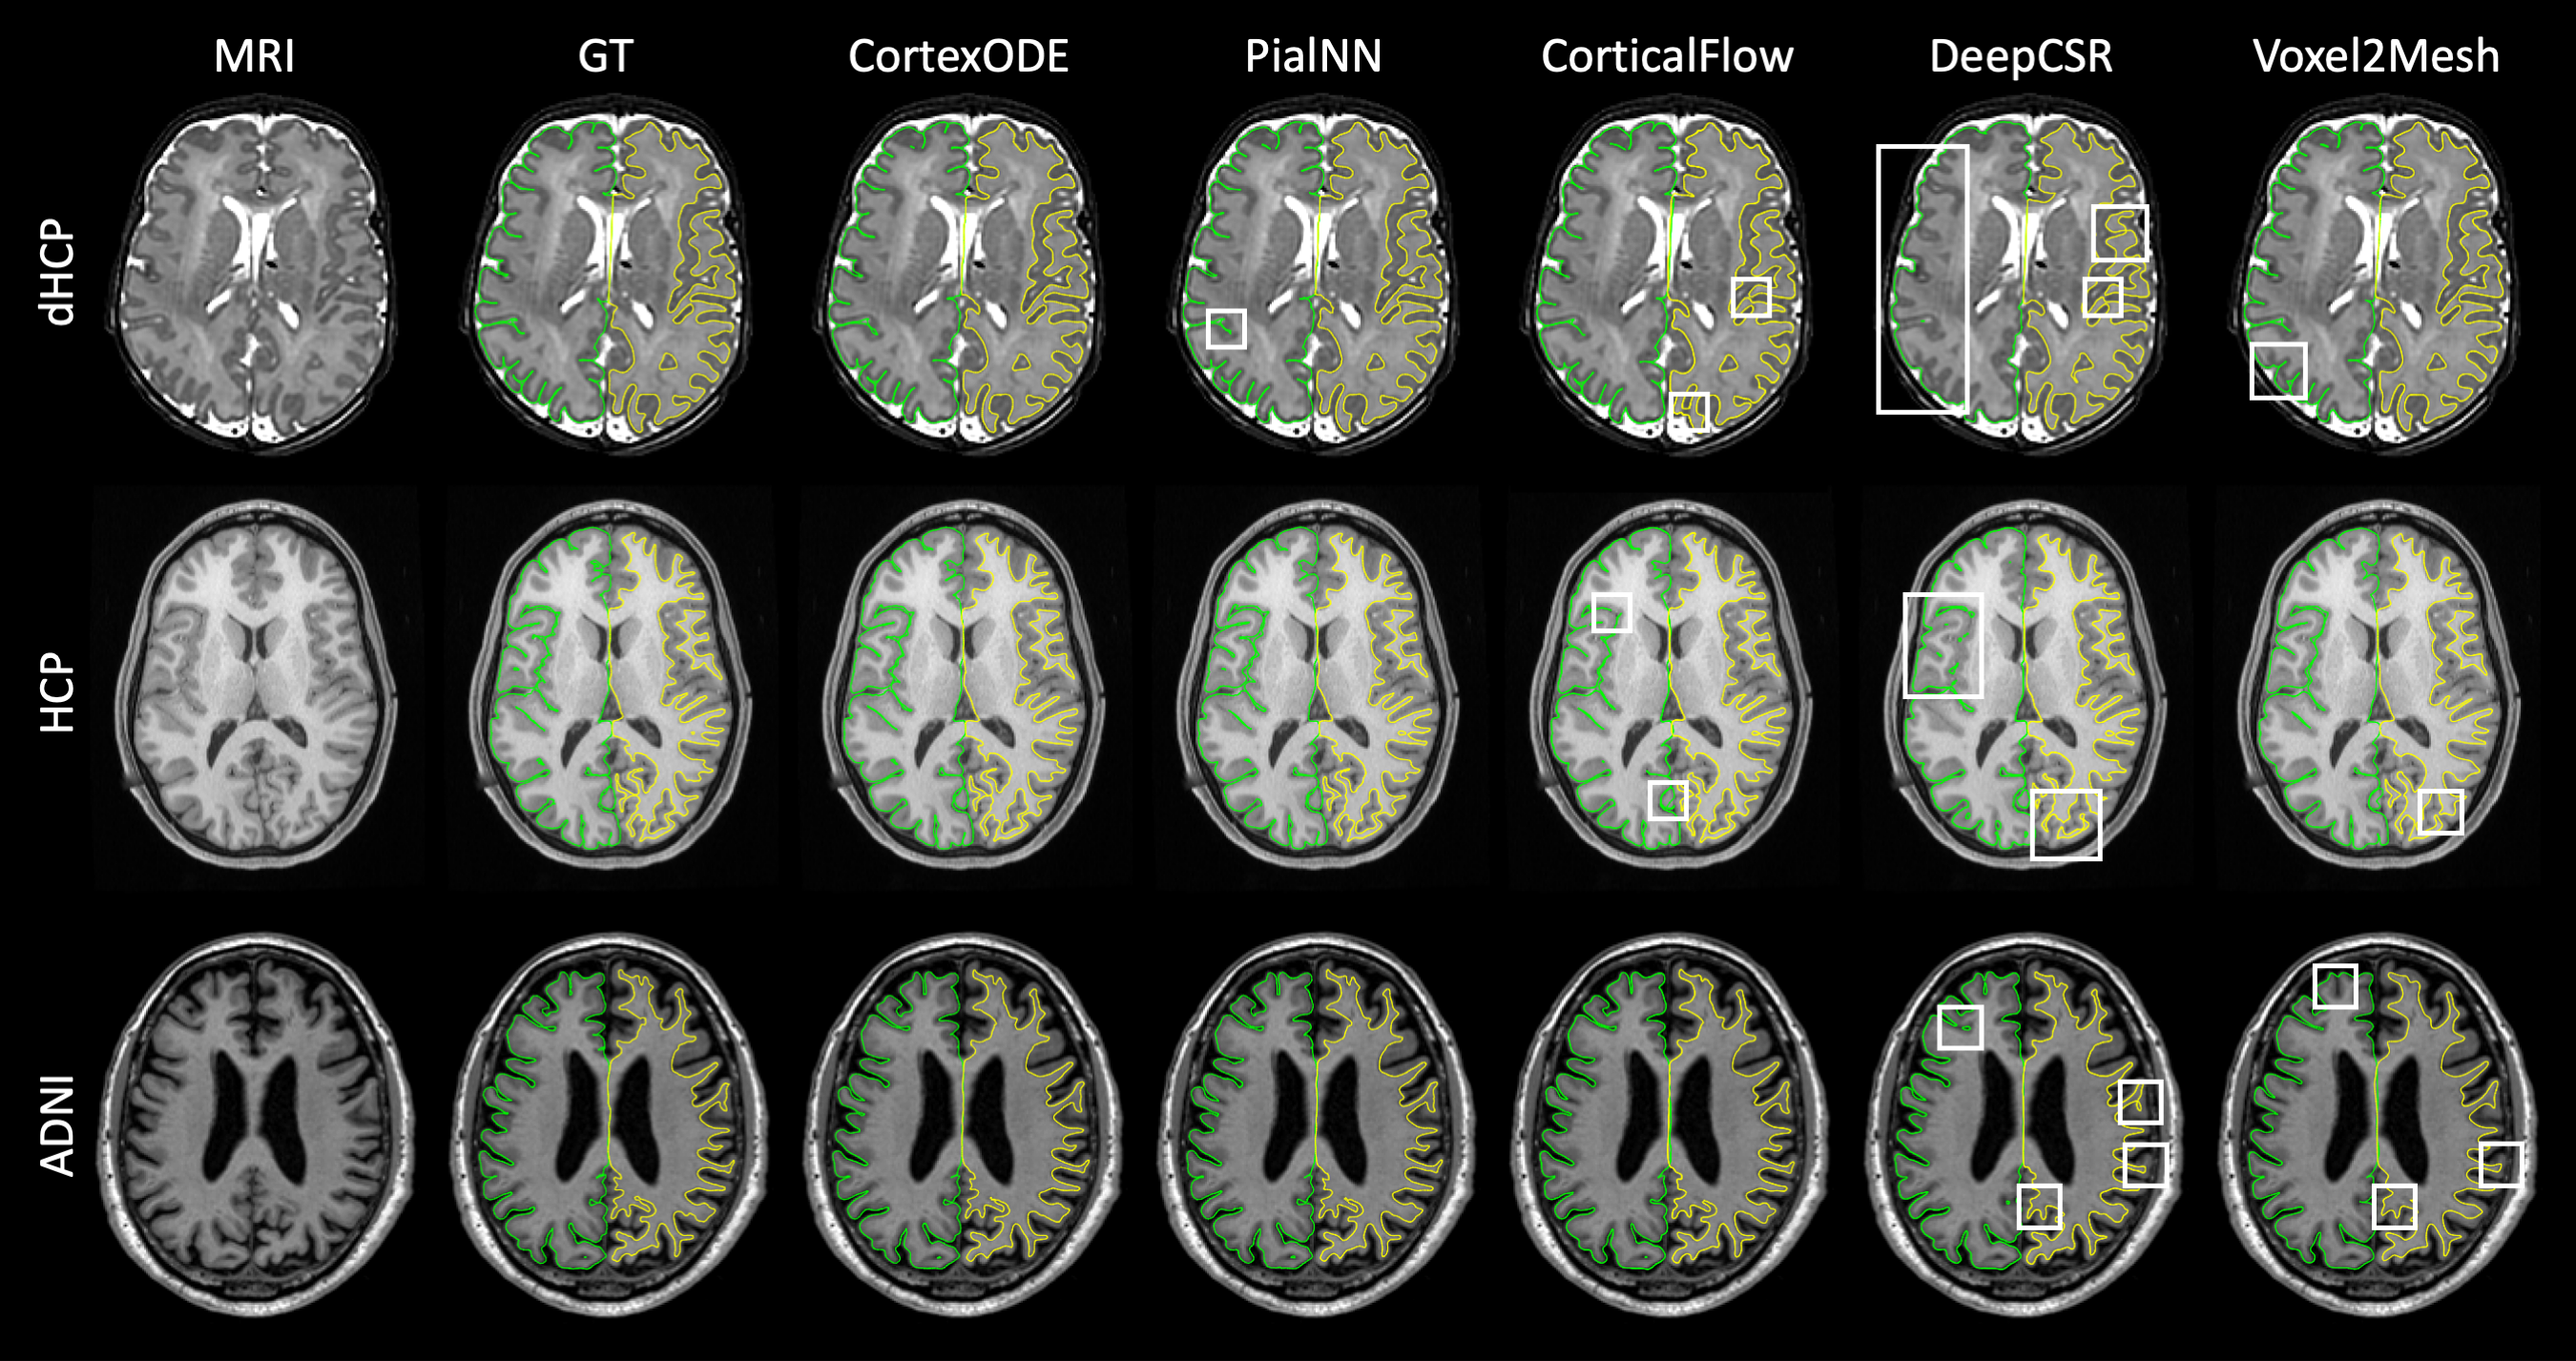

Refer to caption

Figure 5: Visualization of the reconstructed cortical surfaces for dHCP, HCP and ADNI datasets. The geometric error map (blue color) visualizes the distance (from 00 to 1mm1𝑚𝑚1mm) between the predicted surfaces and the ground truth. The artifacts (corruption, self-intersection, partial volume effect, and over-smoothness) on the surfaces are highlighted by different colors.

Figure 6: Visualization of left pial surfaces (green) and right WM surfaces (yellow) projected on the MRI slices. The artifacts are highlighted by white boxes.

4.2.2 Visual Inspection

We visualize the reconstructed cortical surfaces of the subjects in the dHCP, HCP and ADNI datasets. Figure 5 shows the cortical surface meshes with color maps reflecting their geometric errors, and Figure 6 depicts the projected surfaces on the brain MRI slices. The artifacts of the surfaces are highlighted. According to the visualization, the CortexODE-based pipeline produces surfaces with good mesh quality and high geometric accuracy. The results match the ground truth surfaces generated by the traditional pipelines, or even have better mesh quality. The pial surfaces reconstructed by PialNN is not smoothed well and more self-intersections are observed as highlighted. The DeepCSR results are corrupted by partial volume effects in the narrow sulcal regions, especially on the dHCP dataset. The surfaces predicted by Voxel2Mesh tend to be over-smoothed due to the mesh regularization terms.